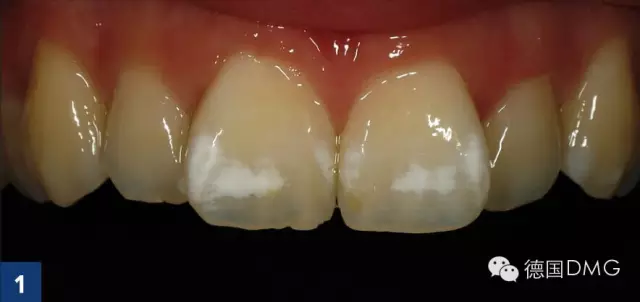

案例1:轻度氟斑牙

Dr. med. dent. Arzu Tuna, Dr. med. dent. UmutBaysal, Dr. Rainer Valentin

作为日常检查的一部分,患者强烈要求对前牙区的白色斑块进行治疗(Fig. 1). 权衡比较了多种治疗方案后, 患者和我们共同选择了渗透治疗。

经大量研究和证据表明,渗透治疗是最适合用于牙正畸后由于牙釉质脱矿造成的白斑病变。根据患者的居住地区和成长经历以及白斑的表现形式,我们将位于牙位11和21的唇面白斑诊断为氟牙症指数0.5(根据Dean的社区氟牙症指数).